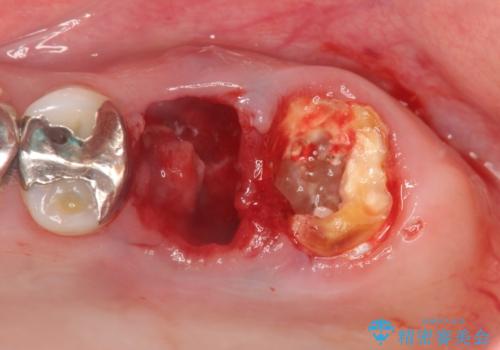

X線検査の結果、左上6には歯根破折、左上7には銀歯の下に大きな虫歯の再発が認められ共に抜歯をせずには症状の改善が見込めない状況です。

奥歯を2本失ったのち、しっかりと噛める環境へと整備するため、しっかりと骨の造成を行い清掃性を高めたインプラント治療を行っていくこととしました。